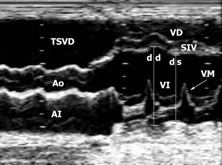

Es la prueba diagnóstica más valiosa y se ha de realizar siempre que se sospeche esta enfermedad.

Los hallazgos principales son los siguientes:

- Hallazgo típico: dilatación de las cavidades afectadas y su forma esferoidal, especialmente del ventrículo izquierdo.

- Las paredes están adelgazadas.

- Disminución difusa de la función contráctil.

- Pese a que la fracción de eyección suele estar baja, el gasto cardíaco en estos pacientes puede ser normal. Esto se debe a que los volúmenes de eyección están muy aumentados y además existe una taquicardia compensadora.

Otros hallazgos:

- Presencia de trombos en el ápex ventricular.

- Derrame pericárdico ligero.

Ecocardiografía 2D. Marcada dilatación de las cavidades cardíacas.

Ecocardiografía modo M. Severa dilatación de los diámetros diastólicos (dd) y sistólicos (ds) del ventrículo izquierdo (VI) con pobre contractilidad.